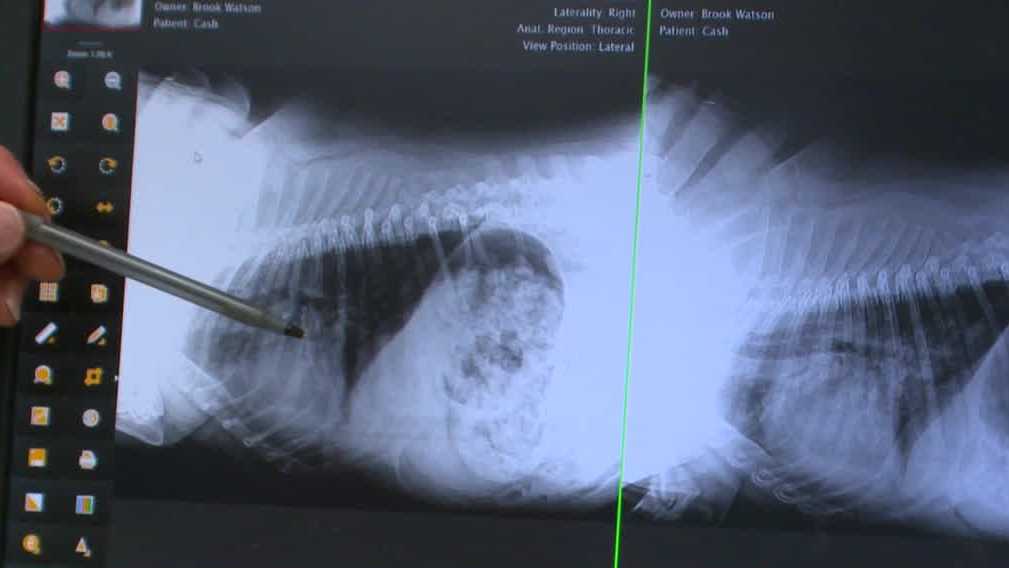

Veterinarians tackle mystery dog illness with COVID-19 drug

A veterinarian in Iowa is prescribing the COVID-19 drug Paxlovid to treat a mysterious dog illness that is spreading across the United States. The veterinarian noticed that many of the severe cases he treated had owners who recently had COVID-19, and he observed similarities between COVID-19 symptoms and the symptoms in dogs. After trying the drug on a severely ill dog named Cash, the dog showed signs of recovery. The veterinarian is now testing the treatment on other dogs with severe cases of the illness.